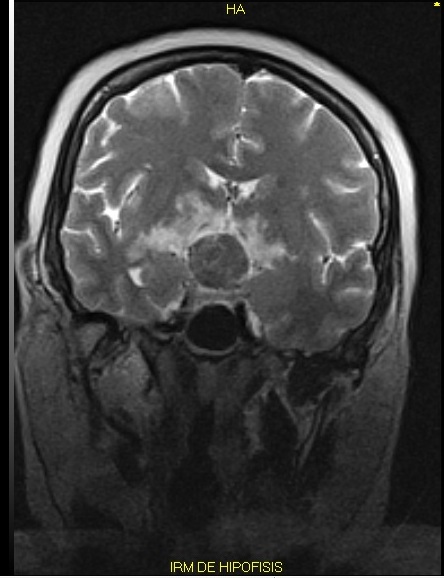

5. RMN de hipofisis

| Asunto | |

| Tipo | Instrumentación |

| Ver (62KB) Indexación de metadatos |